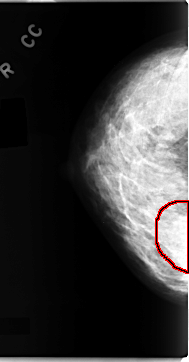

C_0098_1.RIGHT_CC

FILE: C_0098_1.RIGHT_CC.OVERLAY

TOTAL_ABNORMALITIES 1

ABNORMALITY 1

LESION_TYPE MASS SHAPE IRREGULAR MARGINS ILL_DEFINED

ASSESSMENT 4

SUBTLETY 3

PATHOLOGY MALIGNANT

TOTAL_OUTLINES 1

BOUNDARY